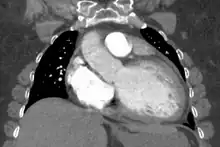

Generalized enlargement of the heart is seen upon normal chest X-ray. Pleural effusion may also be noticed, which is due to pulmonary venous hypertension.

The electrocardiogram often shows sinus tachycardia or atrial fibrillation, ventricular arrhythmias, left atrial enlargement, and sometimes intraventricular conduction defects and low voltage. When left bundle-branch block (LBBB) is accompanied by right axis deviation (RAD), the rare combination is considered to be highly suggestive of dilated or congestive cardiomyopathy.[27][28] Echocardiogram shows left ventricular dilatation with normal or thinned walls and reduced ejection fraction. Cardiac catheterization and coronary angiography are often performed to exclude ischemic heart disease.

Cardiac magnetic resonance imaging (cardiac MRI) may also provide helpful diagnostic information in patients with dilated cardiomyopathy.[30]